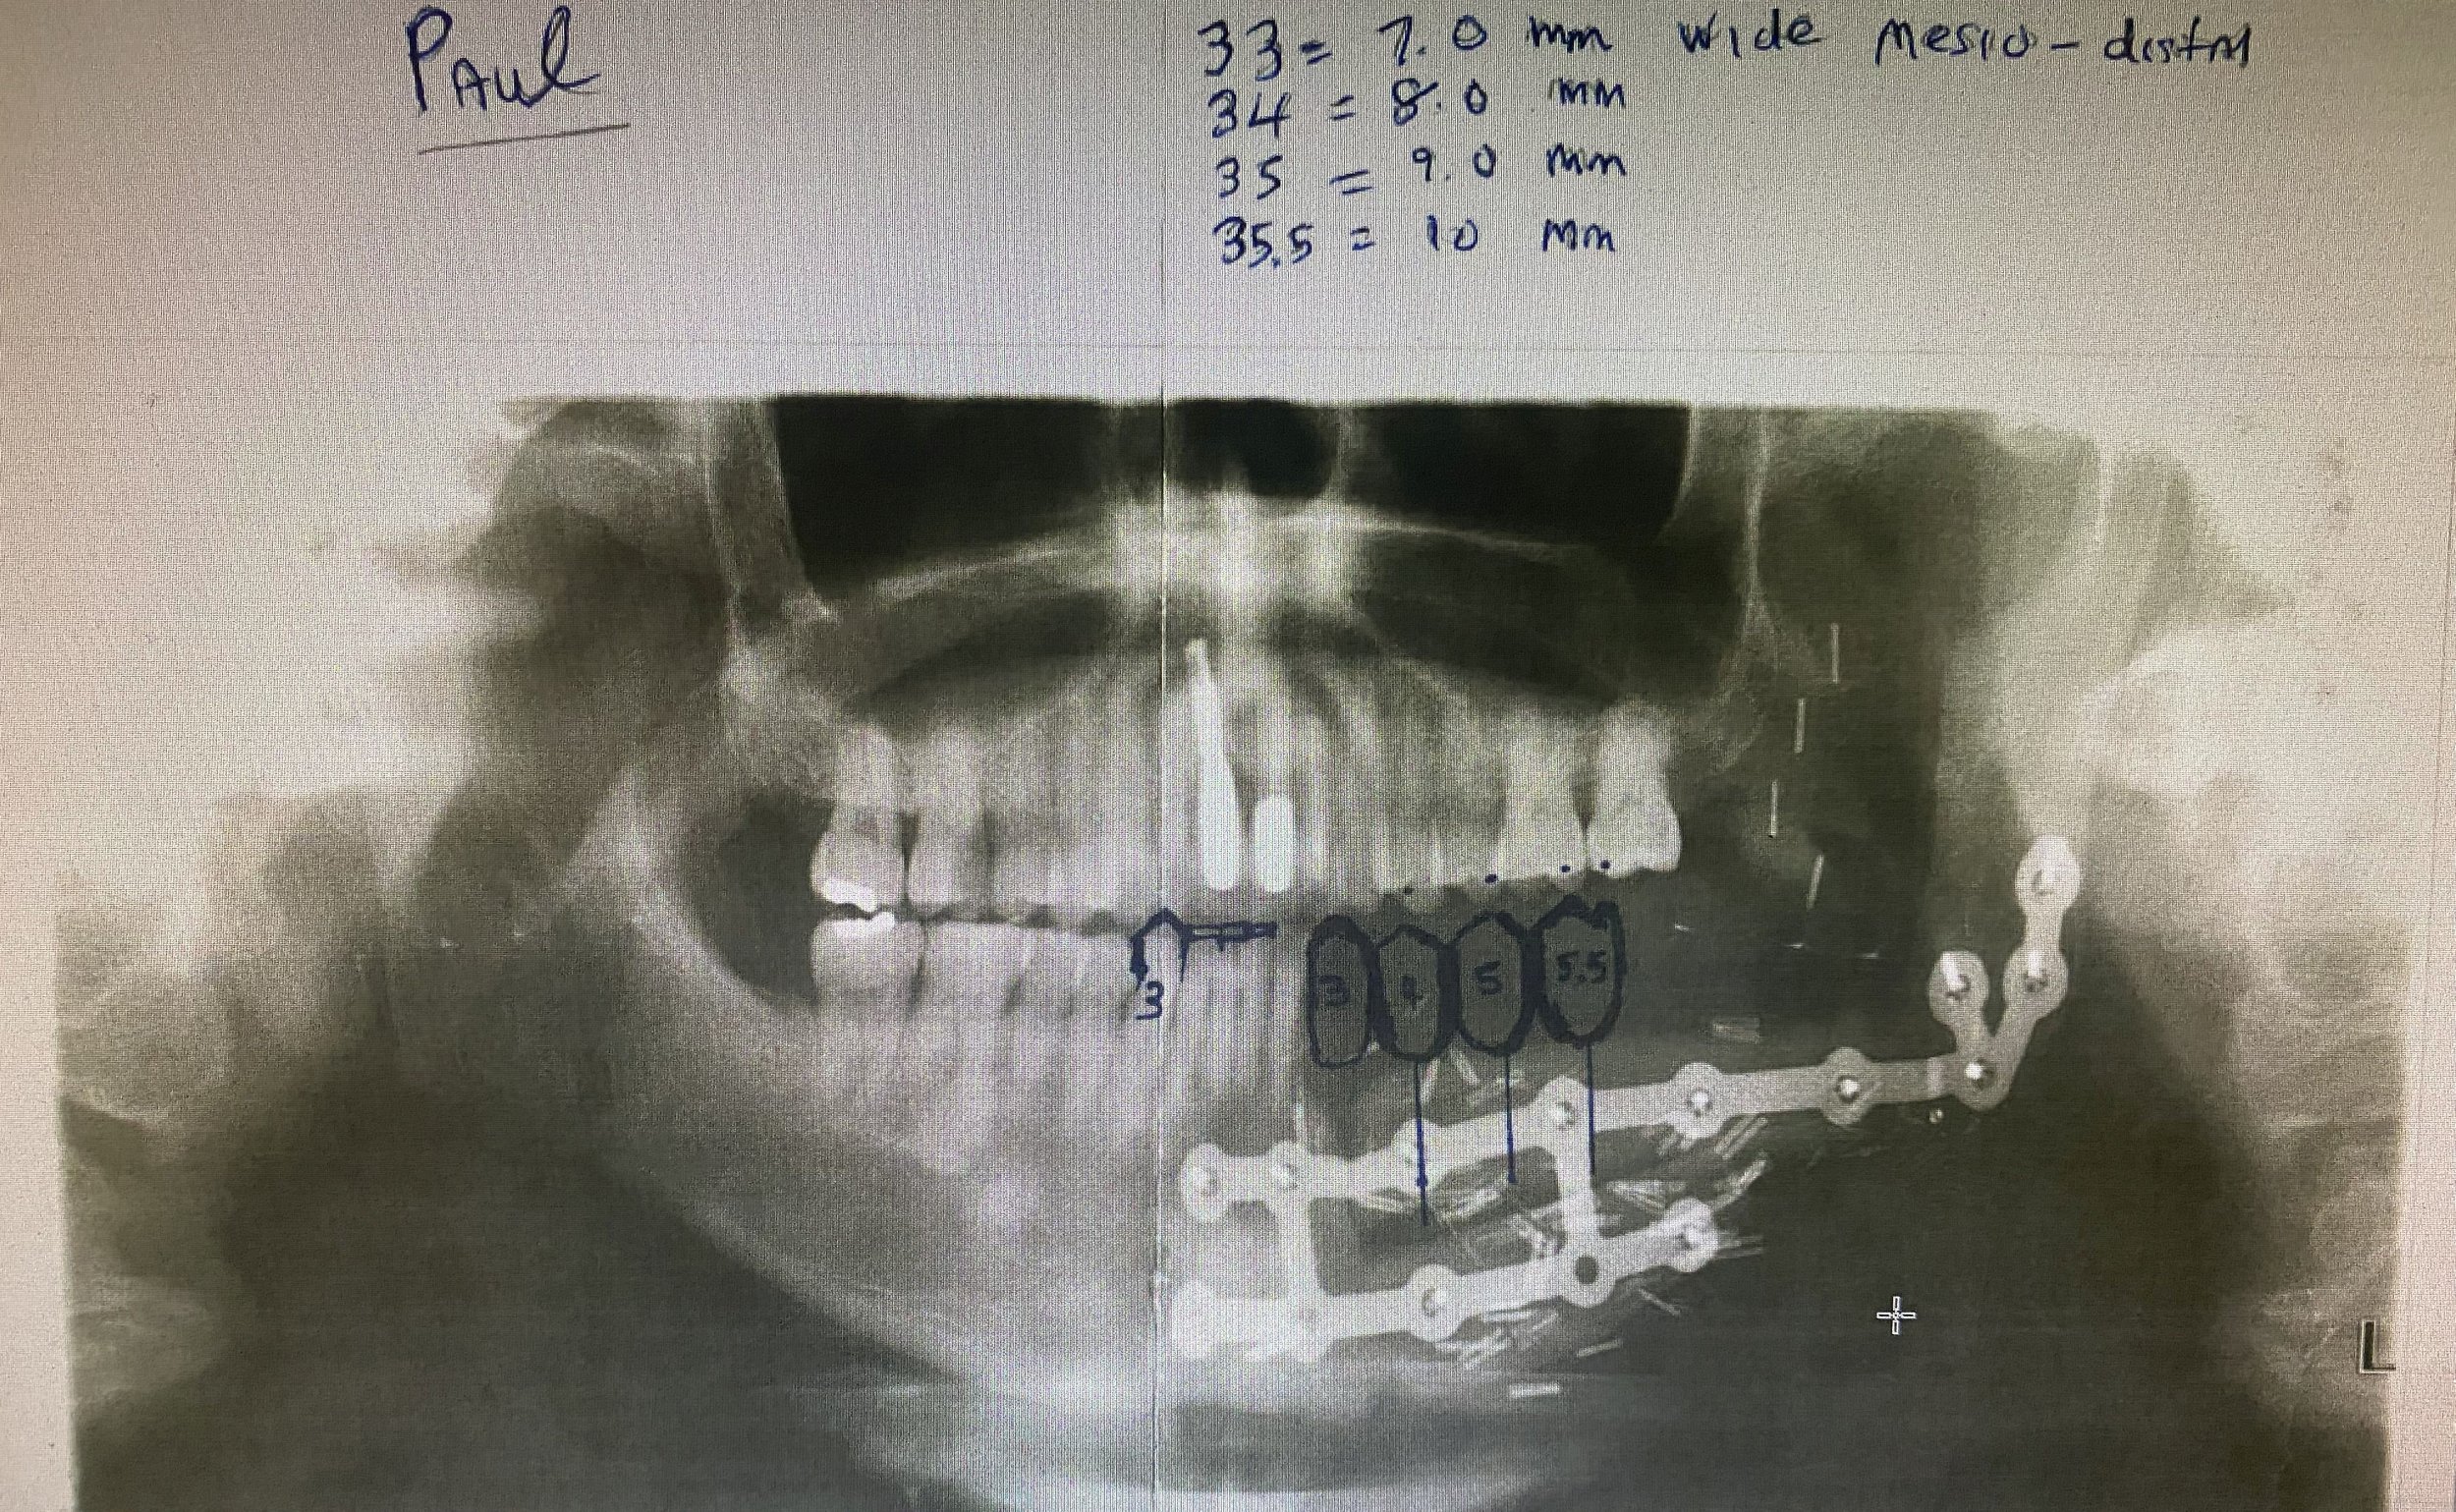

The patient was referred to me at Lismore in 2021 to replace the missing teeth with a fixed prosthesis involving an implant bridge. I designed the bridge on an OPG radiograph and issued instructions to my ceramist technician to fabricate a diagnostic wax up of the future teeth .

-

A surgical guiding device was fabricated with radiographic markers (vertical pink GP points) placed in the centre of the teeth to demarcate the future centroid position of the implant fixtures .

This OPG radiograph illustrates the completed 3 implant fixture and note that two of the metal splints had to be removed for implant placement. Note there was insufficient bone in the lower left canine region to place an implant which necessitated the designing of a cantilevered bridge tooth